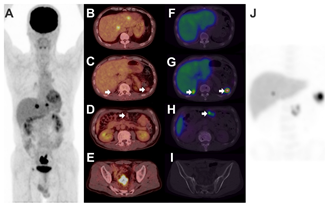

Splenosis Mimicking Peritoneal Seeding of Advanced Colon Cancer Can Be Identified by Spleen SPECT/CT and FDG PET/CT